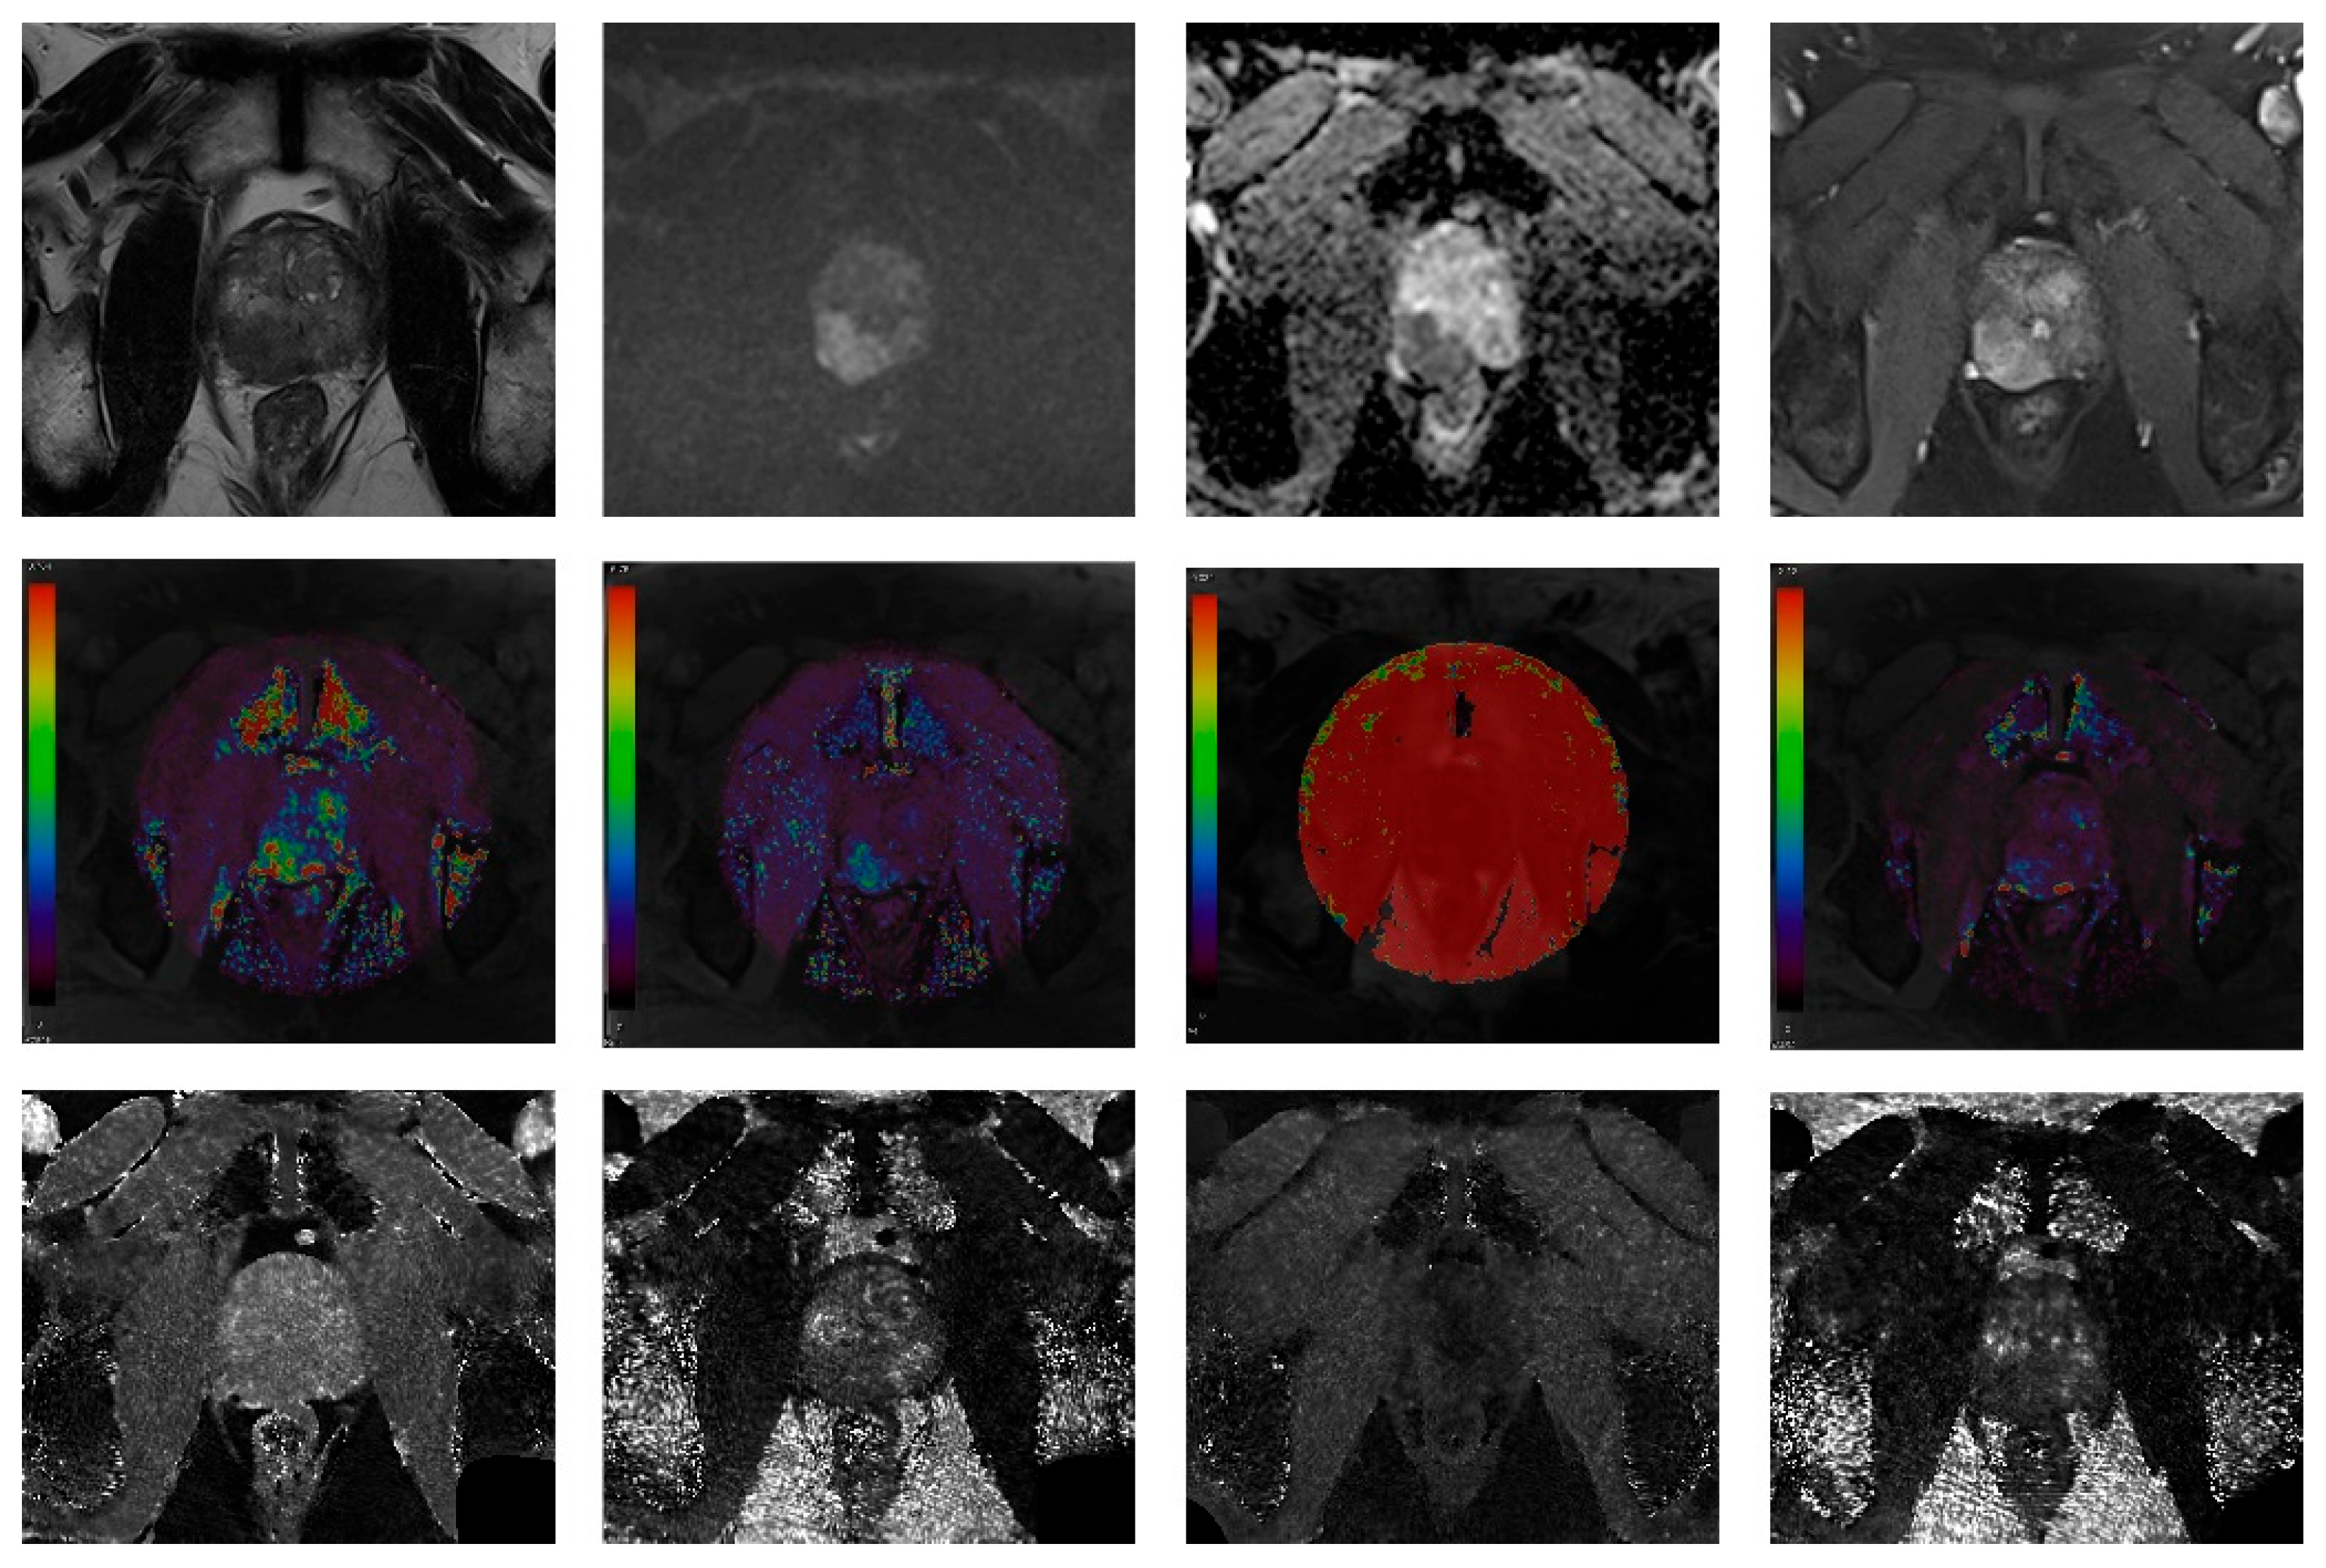

2.3. Image Analysis